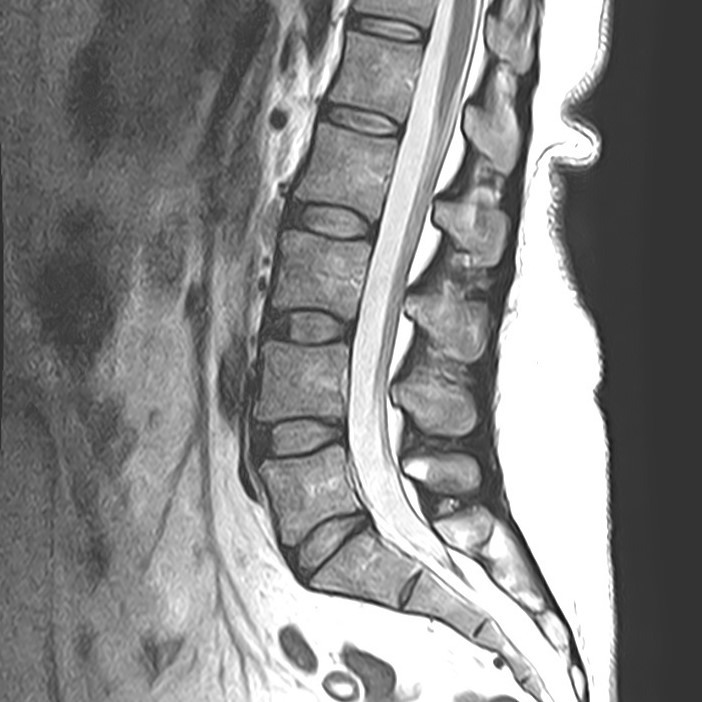

Наиболее точным и эффективным способом диагностики причин появления болей в нижней части спины является МРТ пояснично-крестцового отдела позвоночника. С помощью данного метода можно оценить состояние всех анатомических структур позвоночного столба на исследуемом уровне, безошибочно выявить происхождение болевого синдрома и назначить своевременное лечение.

Многим пациентам интересно, что показывает МРТ пояснично-крестцового отдела. Высокая детальность получаемых с помощью МР-диагностики изображений позволяет с точностью выявить следующие заболевания, локализующиеся в области поясничного отдела позвоночника:

• протрузии и грыжи межпозвонковых дисков;

• дегенеративные заболевания: остеохондроз, спондилез, спондилоартроз;

• последствия перенесенных травм, такие как компрессионные переломы, подвывихи и смещения позвонков;

• новообразования первичного и вторичного генеза;

воспалительные и деструктивные изменения позвонков и окружающих мягких тканей.